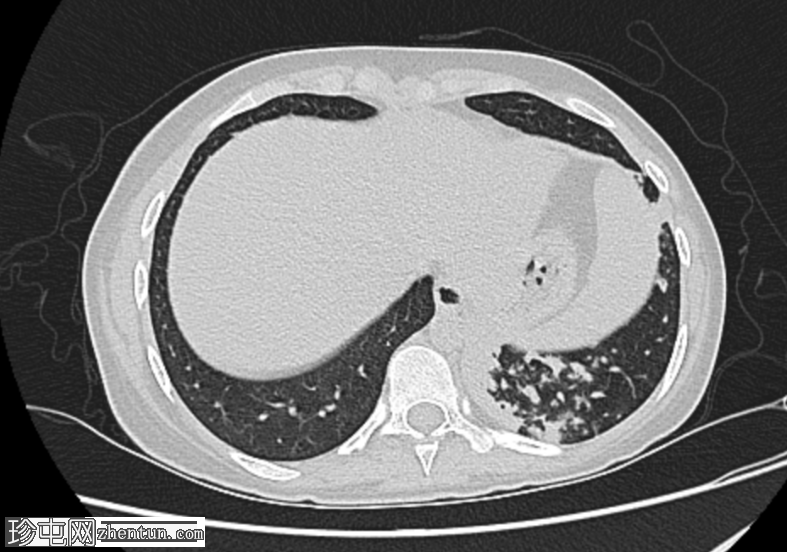

双侧肺部可见气腔实变和空洞,肺壁厚(左上叶和左下叶最大),伴支气管周围增厚,多发树芽征和结节征。

Gene Xpert MTB-RIF 检测,痰液结核杆菌阳性

痰涂片抗酸杆菌(3 份),Z.N 染色阳性